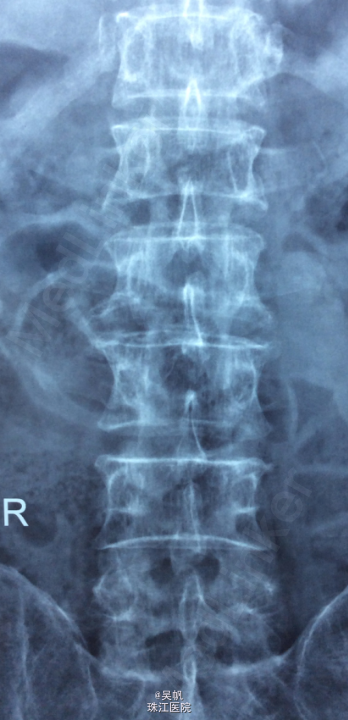

主诉:反复腰痛7年余,加重伴右下肢麻痛半年。 病史:女性患者,56岁。患者7年前在做家务时出现腰部剧烈疼痛,当时腰部活动受限,在外院门诊诊断为腰肌劳损,给予对症治疗,效果较好。7年来活动后腰部均出现疼痛,反复出现。最近半年以来,患者腰部疼痛时间延长,加重,并伴右下肢麻木,放射痛至足踝处。患者一般情况尚可。

查体:腰2/3、腰3/4、腰4/5、腰5/骶1棘间及左右棘旁轻压痛、叩击痛,右侧坐骨神经出口处明显压痛。右小腿外侧感觉略减退,右侧伸膝、踇背伸肌力4级,右侧直腿抬高试验20°(+),加强(+),Lasegue征(+),右侧4字征(+),右侧股神经牵拉试验(+)。双侧Babinski 征及Oppenheim 征(-)。 辅助检查:三大常规、血生化、肝肾功能均未见明显异常。患者腰椎动力位片正常,其余重要腰椎影像学如下。

诊断: 腰椎间盘突出症 (L4/5)。 处理:入院后完善相关检查,术前给予对症治疗,科里术前讨论决定:拟行手术:椎间孔镜下L4/5椎间盘摘除术。